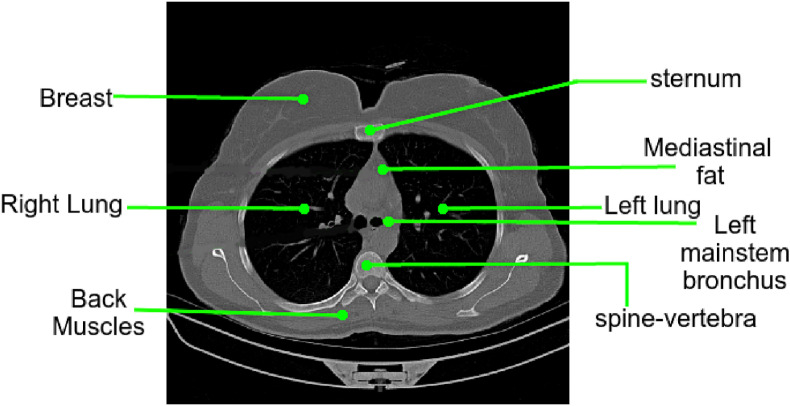

Lung parenchyma refers to the portion of the lungs that is involved in the gas transfer and includes alveoli, alveolar ducts, bronchioles, and other essential tissues. The esophagus, trachea, heart, lungs, diaphragm, thymus gland, aorta, spine, nerves, veins, and arteries are all imaged by the CT scan. Furthermore, the method proposed in this paper generates a heatmap only for detecting COVID-19 findings in the lungs. As a result, the region concerned with COVID-19 diagnosis is the lungs, and the rest organs must be segmented from the CT scan for a clear view of any COVID-19-related findings. An annotated image of the chest CT scan is shown in Fig. 3 . This algorithm is proposed to resolve this complex orientation into a simpler view of the lungs.

Fig. 3.

A CT image slice from the dataset shows the complex orientation of a regular CT image which makes the diagnosis difficult owing to stressed visibility of lungs parenchyma.